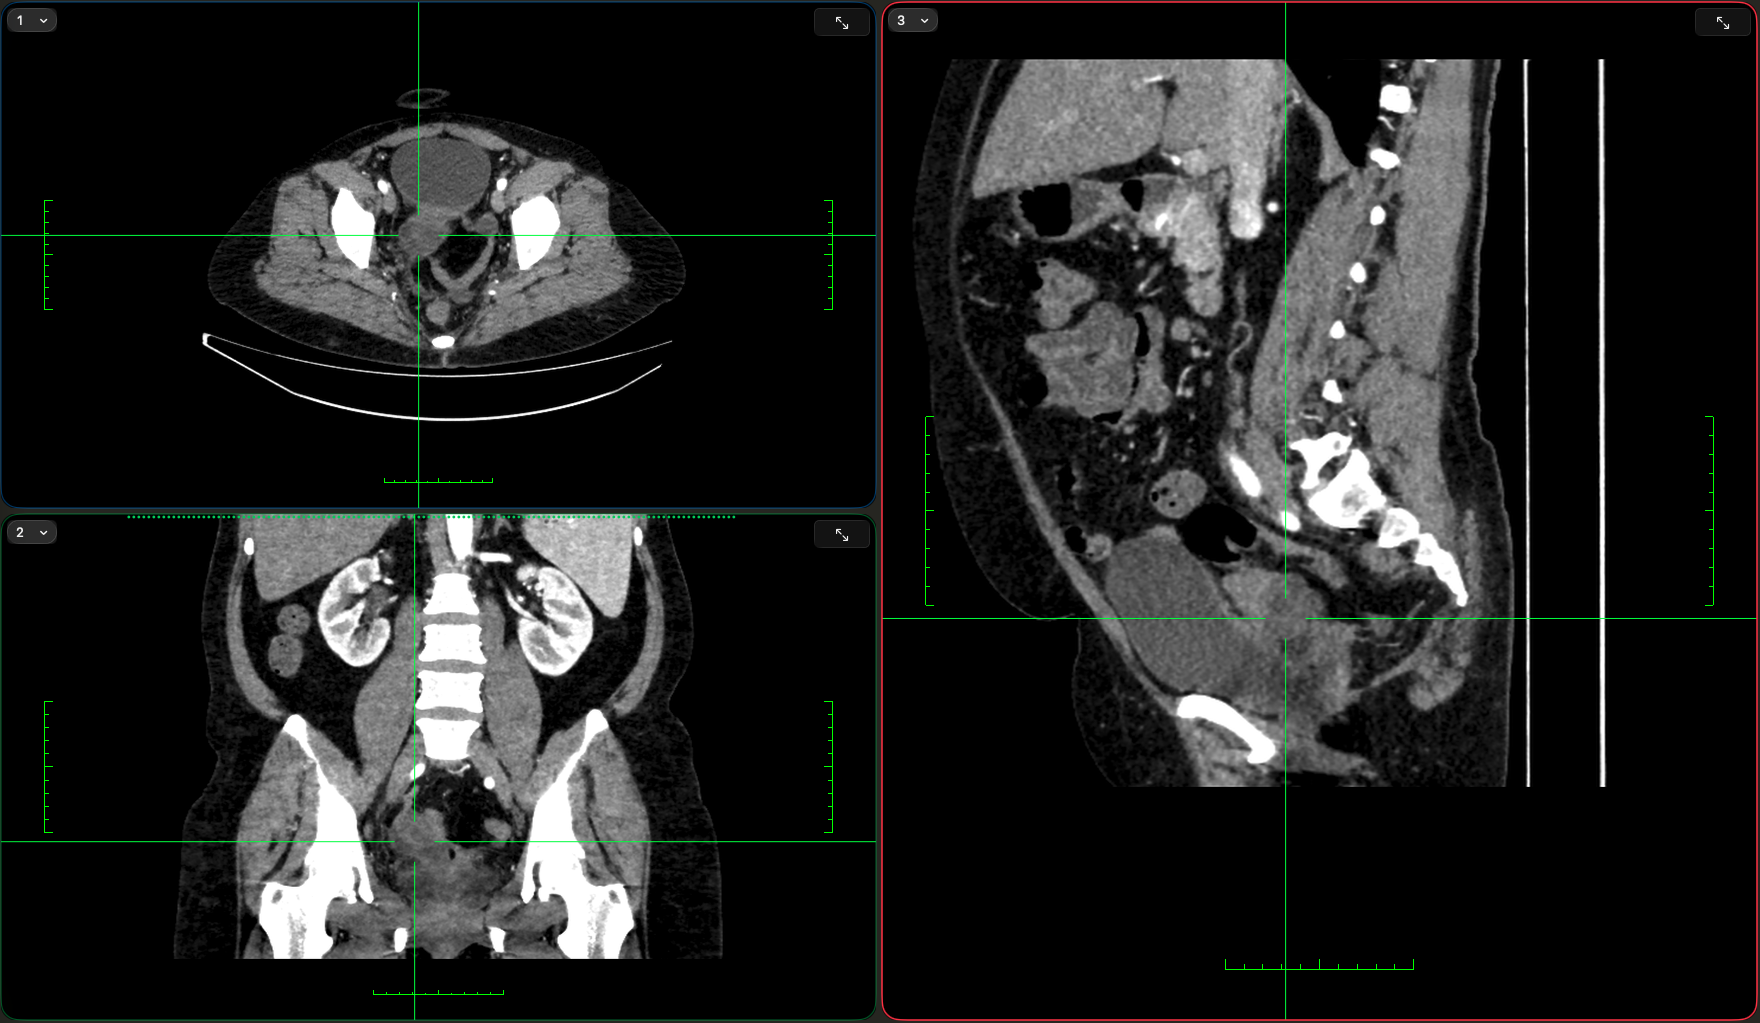

Пацієнтка 53 роки.

В анамнезі — екстирпація матки (12.2024) з приводу міоми.

Протягом року — ознаки хронічного запального процесу кукси піхви, виділення післяопераційних лігатур, проведення протизапальної терапії.

Після переохолодження — гострий початок:

• тягнучий біль унизу живота

• підвищення температури до 38.5°C

• за результатами дообстеження — утворення запального характеру в порожнині таза із залученням додатків

📌 Діагноз:

Тубооваріальне утворення додатків матки.

Відмежований хронічний тазовий перитоніт.

Лапароскопія. Видалення запального тубооваріального утворення додатків матки в умовах відмежованого хронічного тазового перитоніту. Санація черевної порожнини.

✔ розбір МРТ та клінічного висновку (зображення будуть доступні на сайті)